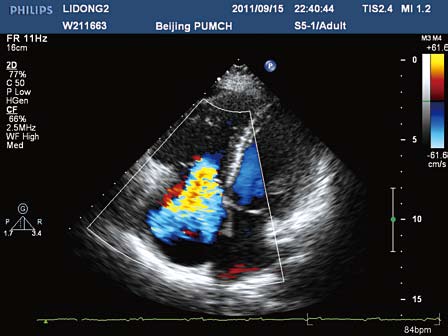

超声心动图和彩超区别

超声心动图和彩超区别,超声心动图和心脏彩超

超声心动图和心脏彩超

超声心动图与心脏彩超

心脏超声心动图

超声心动图图片